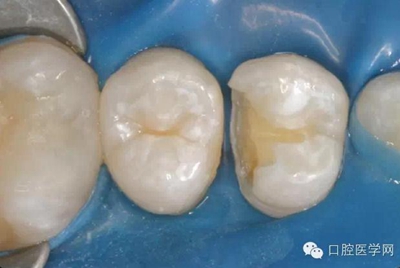

在根管治療之前我們要做麻醉,所以整個治療的過程是不疼的。治療過程中要使用橡皮障,只露出要治療的牙齒,口腔其他部分都在橡皮障之下,可以隔開唾液,因為唾液里也是有細菌的,如果一邊清理,一遍有唾液流到根管內(nèi)部,那么就無法做到完全無菌。同時,有橡皮障的隔絕作用,可以防止治療器械掉到嗓子里,這一點非常重要。